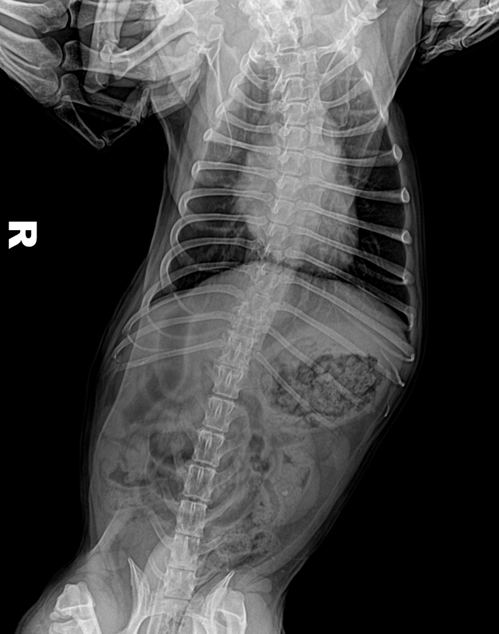

(2)识别X线影像中的颈椎、胸椎、腰椎和荐椎,并能确定属于位置(图6-12、图6-13)。

(3)识别椎间隙、椎间孔、棘突、横突的X线影像(图6-12、6-13)。

犬、猫正常脊柱由7节颈椎、13节胸椎、7节腰椎、3节荐椎和数量不定的尾椎连接而成。各椎骨间有椎间盘,但第1~2颈椎关节、3节荐椎之间无椎间盘。椎间盘由髓核和纤维环组成,呈软组织阴影,在X线片上表现为低密度的裂隙。邻近的椎间隙大致相等,但正常的第10~11腰椎椎间隙较狭窄。

犬椎体侧位投照显示似方形,多数脊椎可显示椎弓、椎管的背侧缘与腹侧缘、椎体前后端骨骺、棘突、横突和椎体。猫的椎体较长,侧位显示似长方形,椎弓根、关节突欠清楚,椎间孔背侧缘不如犬易见。棘突在腹背位投照时呈致密狭长的断面高密度阴影。侧位投照时,相连椎骨的大小、形状和密度大致相同。第2颈椎棘突靠近第1颈椎椎弓,或与之重叠。第6颈椎横突宽大,呈翼状。胸椎椎体长度略比颈椎椎体短。第11胸椎棘突垂直向上,称为直椎。直椎之前的胸椎棘突斜向后上方,而直椎以后的胸腰椎棘突则斜向前上方。后段4~5节胸椎的的关节后突下方、椎间孔的前上界处,可显示一细小、类三角形的副突阴影。